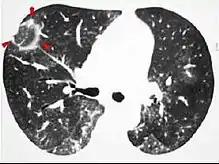

CT image showing ground-glass opacification in the posterior of the right lung (screen left). - Measles

CT image showing diffuse GGOs throughout both lungs. An abscess is also noted in the right lung (screen left). - Adenocarcinoma in situ of the lung